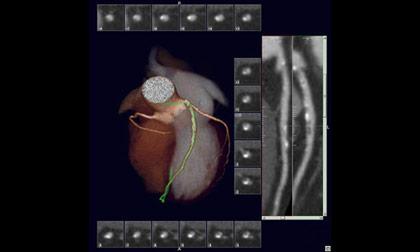

CTA Coronary Artery (Coronary Computed Tomographic Angiography)

การฉีดสีเพื่อตรวจหลอดเลือดหัวใจโดยใช้ MDCT 64 Slices เป็นการตรวจเพื่อค้นหาภาวะหลอดเลือดหัวใจตีบ โดยสามารถบอกระดับความรุนแรงของการตีบของหลอดเลือดที่ไปเลี้ยงกล้ามเนื้อหัวใจได้ หรือใช้ติดตามผลการรักษาในรายที่เคยมีประวัติผ่าตัดหลอดเลือดหัวใจมาก่อน รวมถึงการหาความผิดปกติแต่กำเนิดของหลอดเลือดหัวใจ โดยในปัจจุบันเป็นการตรวจคัดกรองในผู้ป่วยที่มีความเสี่ยง การเตรียมผู้ป่วยที่มีปัจจัยเสี่ยงการเกิดโรคหัวใจ ก่อนทำการผ่าตัดหรือทำหัตถการใหญ่ๆ